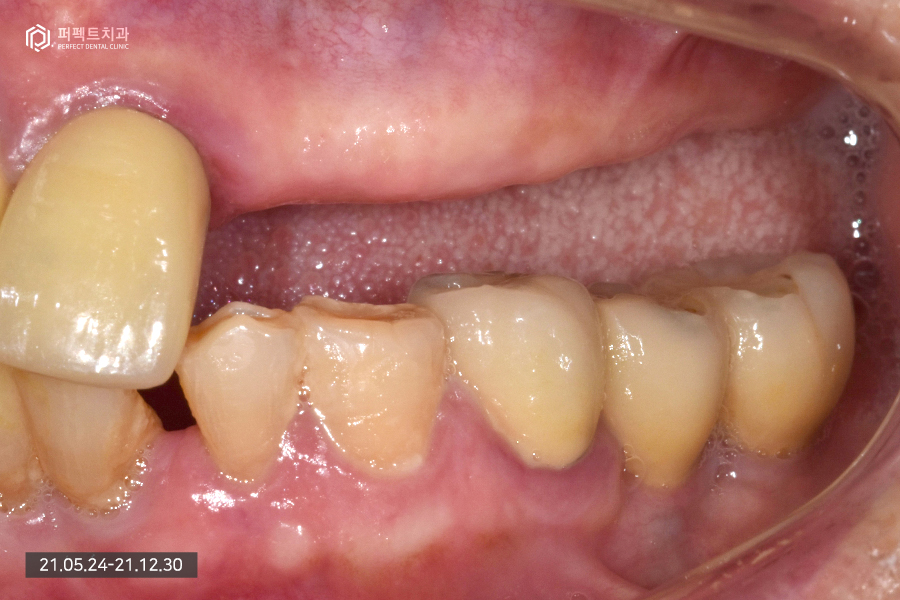

내원 당시 초진 사진입니다.

80대 여성 환자분으로 연세가 많은 편이셔서 앞니는 몇 개 남지 않았고 어금니는 아예 없는 상태였습니다.

남아있는 앞니의 경우 3개가 남아있고 하나는 걸어서 사용하고 있는 상황이었는데 앞니가 심하게 흔들리고 있는 상황이라 모두 발치 하기로 결정을 하였습니다. 이런 경우 윗니는 치아가 하나도 없는 상태가 되어 전체 임플란트로 수복하게 됩니다.

아래 치아의 경우 멀쩡한 것처럼 보이지만 실제로는 그렇지 않습니다. 발치를 해야하는 치아들도 있고 치아가 없는 부분은 임플란트로 수복하기로 하였습니다.